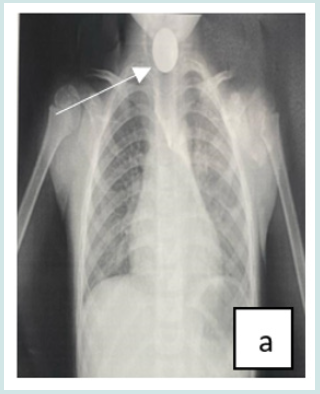

Cervico-thoracic X-ray performed in 211 cases (99%) showed opacity in 209 cases (99%). In one case, 2 circular opacities were observed, one of which had a double contour, indicating the ingestion of 2 foreign bodies (Figure 1: a, b, c, d, e, f). Foreign objects were a coin in 182 cases (85.4%), a shirt button in 4 cases (1.88%), a food in 7 cases (3.27%), and a flat battery in 3 cases (1.41%) (Table III). In 2 cases (1%) the EC was radiolucent.

Figure 1: Front cervico-thoracic radiograph showing different radiopaque foreign bodies (a,b,c,d,e,f). a: Circular esophageal CE of metallic tone, round opacity (coin).